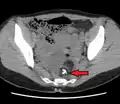

A complex cyst due to a dermoid as seen on ultrasound

A complex cyst due to a dermoid as seen on CT. Arrow points to bone or teeth.